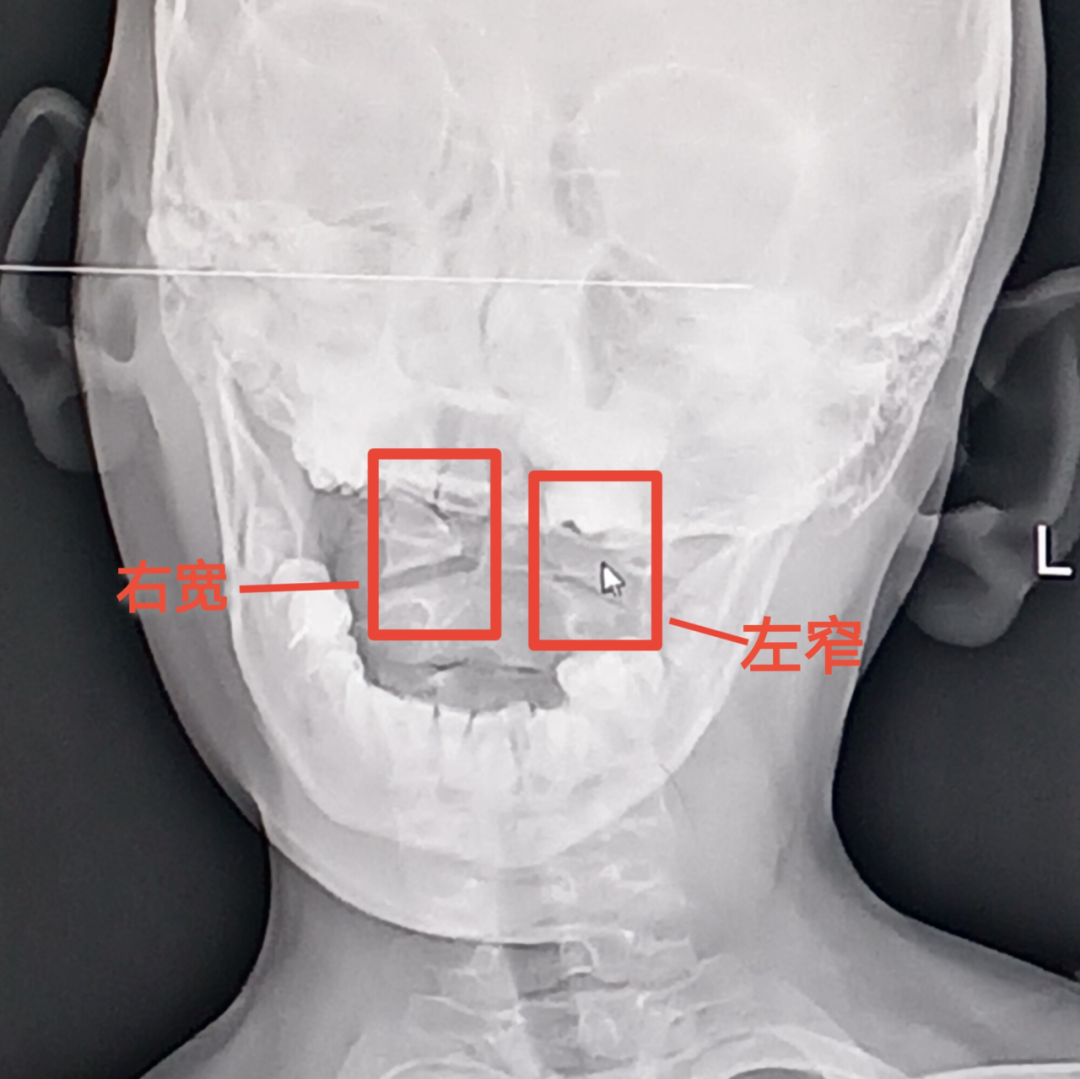

2.影像学检查:为确定寰枢关节脱位的主要依据。颈椎开口位X线片显示寰齿间距不等宽。

颈椎CT平扫

提示:齿状突与寰椎两侧块之间的距离不相等。